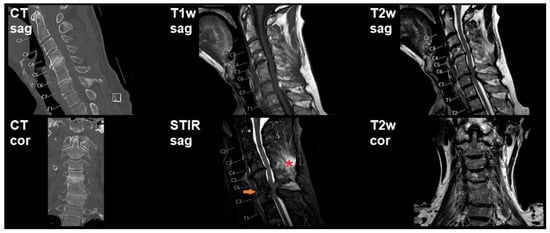

3.2. Imaging and Intraoperative Findings